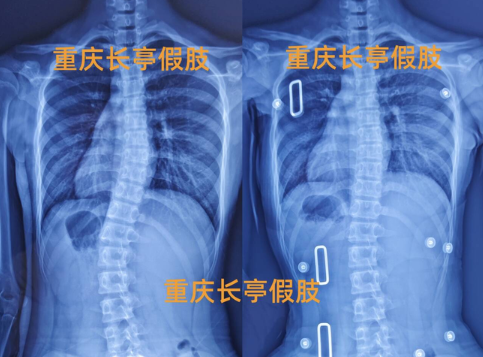

脊柱侧弯

11岁脊柱侧弯

10岁女孩脊柱侧弯矫正